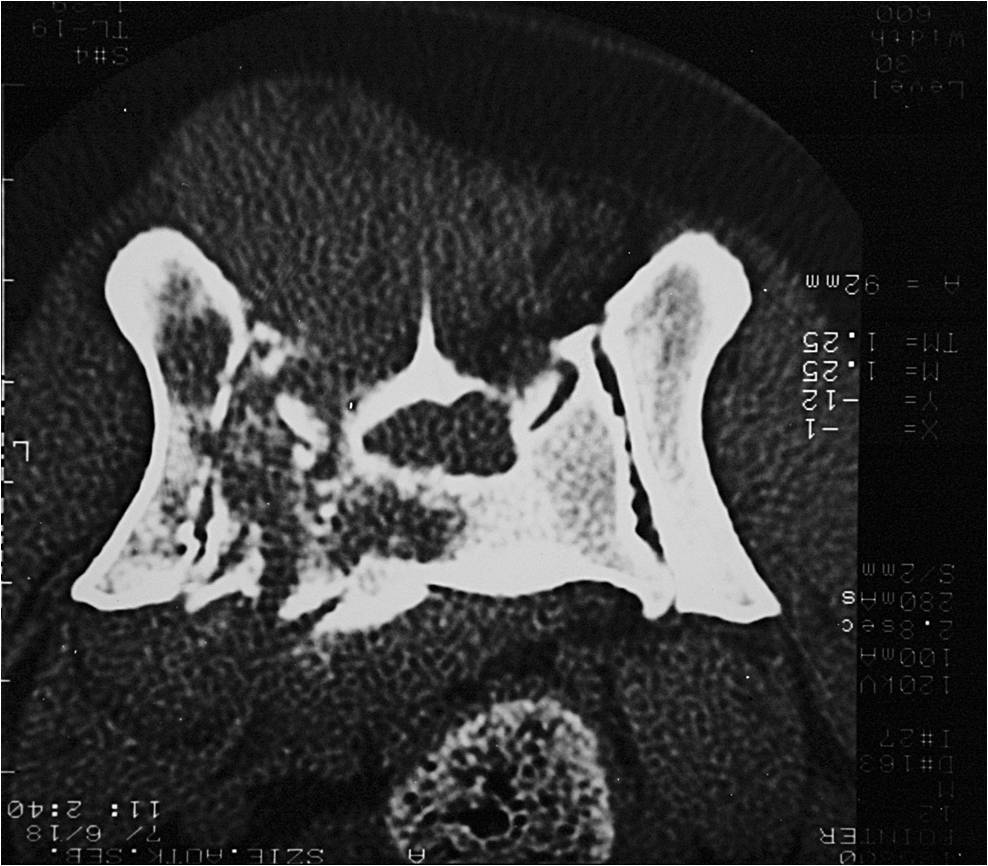

a CT, így számos betegség megállapítható. Különösen a kistestű fajtákban gyakori agyvelővízkór (2. ábra), és a más fajtákban is előforduló agydaganatok (3.ábra) egy része állapítható meg nagy biztonsággal.

A koponyán belüli vérzések és a koponya traumás sérülései (4. ábra) is jól kimutathatóak. Hasonlóan fontos szerepe van a közép-, és belsőfül betegségeinek megállapításában, mert biztosan felismerhető a